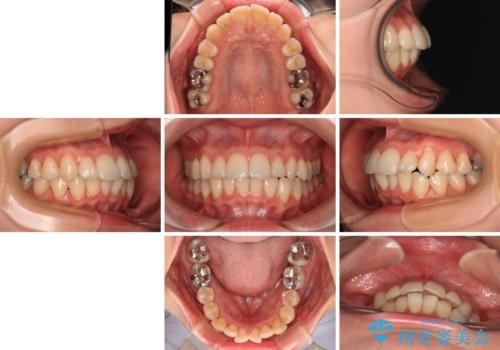

- 矯正装置

- 審美装置

- 治療期間

- 1年3ヶ月

- 前歯のデコボコや、やや突出した感じを気にして来院された患者様です。

抜歯矯正を必要とするほど口元の突出感はなく、本人もそこまでは気にしていない様子でした。

お仕事柄、マウスピース装着は困難とのことで、表側のワイヤー矯正にて治療を行うこととしました。

デコボコ解消の際に、前歯が前突するリスクがあったため、舌突出癖の改善と、アンカースクリューによる加強固定を行うこととしました。

矯正治療後には奥歯の銀歯やむし歯をセラミックやゴールドにて治療を行い、大変整った口腔環境へと改善さ。れました